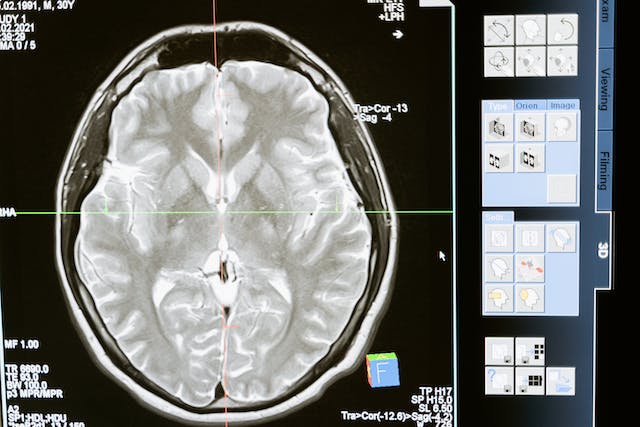

- 영상 진단 검사: MRI, CT, PET 등의 영상 진단 검사를 통해 뇌의 구조적 이상을 찾아낼 수 있습니다. 이러한 검사는 뇌의 손상, 종양, 뇌혈관 이상 등을 확인하는 데 도움이 돼요.